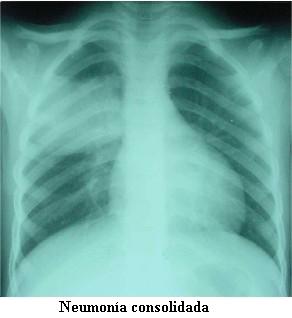

Estudios de base poblacional sobre la neumonía del niño adquirida en la comunidad son escasos en América latina y la epidemiología de S pneumoniae está pobremente establecida debido a la baja sensibilidad de las técnicas bacteriológicas. Para subsanar esas limitaciones la Organización Mundial de la Salud recomendó la interpretación estandarizada de las radiografías de tórax de los niños como una herramienta epidemiológica idónea para proporcionar datos sobre la carga de enfermedad que representan las neumonías bacterianas. Para ese propósito OMS/CDC propuso un protocolo genérico que fue adoptado en Uruguay.

Sse llevó a cabo tres años de vigilancia en cuatro hospitales de ambos departamentos cubriendo 229.128 habitantes, de los cuales 10,2% son menores de 5 años. A cada paciente hospitalizado se le realizó una historia clínica padronizada y se obtuvo una fotografía digital de la radiografía de tórax. Un pediatra y un radiólogo pediatra, con prescindencia de la historia clínica, interpretaron las imágenes digitales que a su vez fueron evaluadas por una comisión internacional de expertos. La etiología bacteriana y viral fue investigada.

De 2.184 pacientes captados, se dispuso para el análisis de 93,1% de las historias clínicas y las fotografías digitales. Según la interpretación radiográfica, 826 (40,6%) fueron neumonías consolidantes, 941 (46,3%) neumonías no consolidantes y 267 no fueron neumonías (13,1%). Los niños menores de dos años de edad predominaron (66,9%), de los cuales 45,8% tuvieron neumonías consolidantes. La tasa de incidencia anual de neumonía consolidante en los niños hospitalizados menores de cinco años fue 1.152 x 105, pero las tasas más altas se registraron en los pacientes menores de dos años.